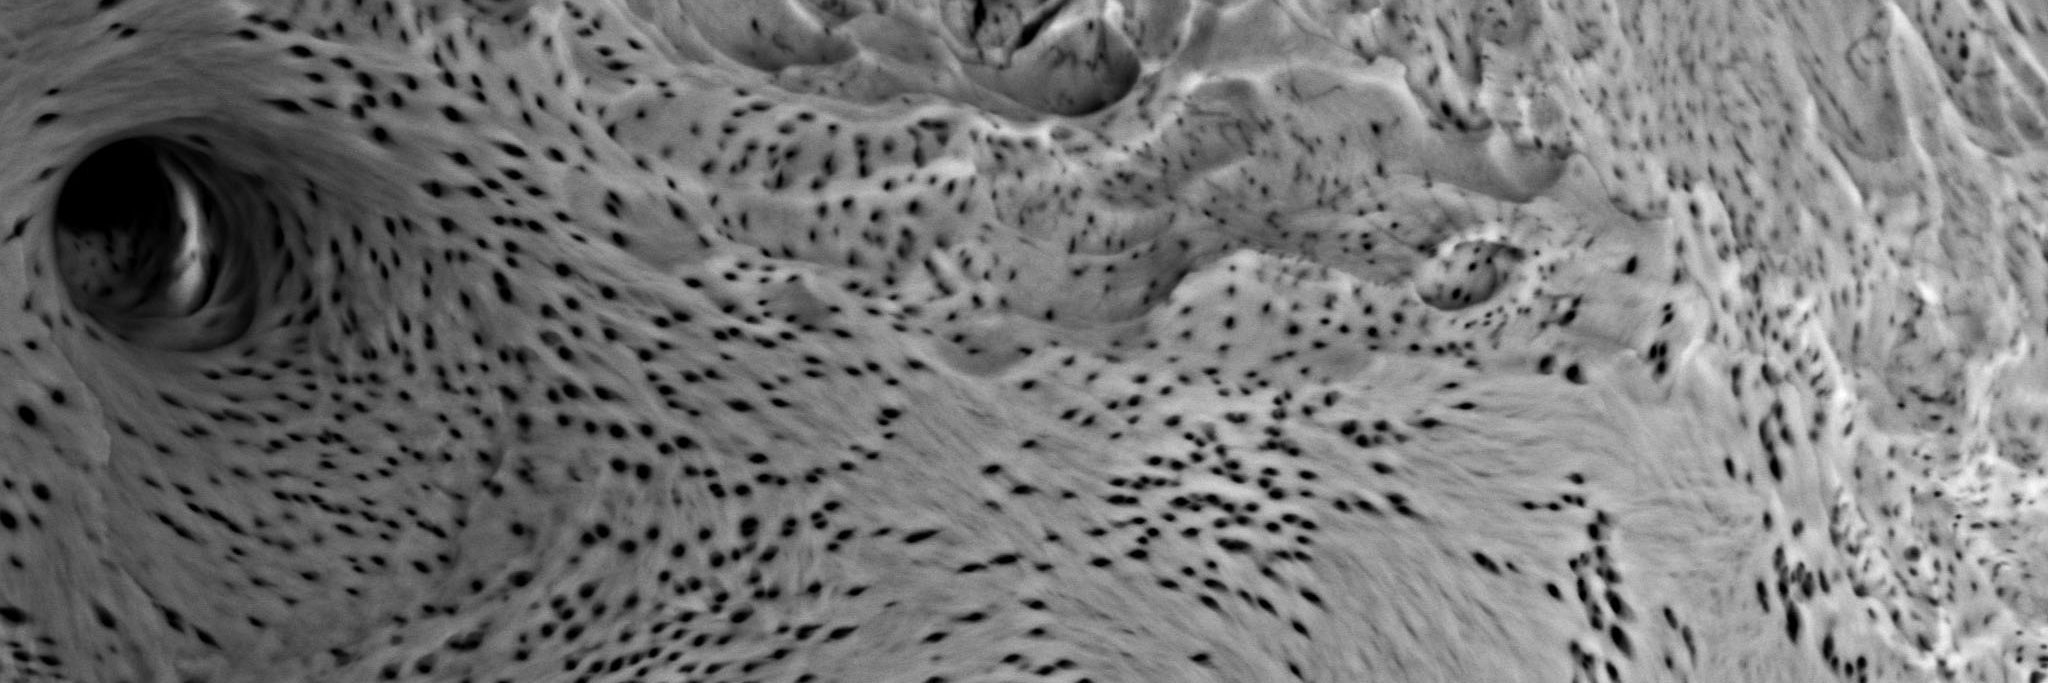

Inquisitor of things. Runner of distance. Post-doctoral researcher in bone and cartilage biology, osteoarthritis and endocrinology at Imperial College